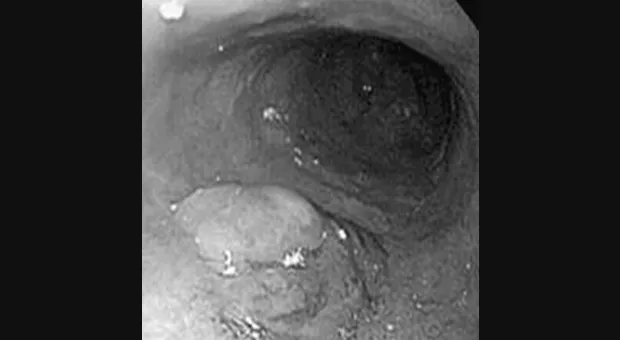

Важность установления стадии

Вовлечение лимфатических узлов непосредственно связанно со стадией Т поражения. Folli с коллегами [22] провел мультицентрическое многоцентровое ретроспективное исследование 584 пациентов с ранним раком желудка перенесших гастрэктомию D1. Только 3,7 % с поражением ограниченным слизистой имели метастазы в лимфатические узлы, тем временем как при вовлечении подслизистого слоя метастазы наблюдались в 25,3 %. Shimada с коллегами [23] провел ретроспективное обследование 1051 пациентов с ранним раком желудка перенесших гастрэктомию с диссекцией лимфатических узлов по D1 или D2. Частота метастазов в лимфатические узлы была 2,3 % для опухолей ограниченных слизистой и 19,8 % при вовлечении подслизистого слоя. Опухоли, ограниченные слизистой оболочкой, имевшие метастазы в лимфатические узлы были изъязвлены. Авторы сделали вывод, что все пациенты с опухолью ограниченной слизистой оболочкой и без изъязвления должны рассматриваться как кандидаты на EMR. Кроме характера поверхности опухоли важны границы от краев препарата до опухолевых клеток [24]. Японские исследователи показали [25], что уровень рецидива равен 0 % при границе 2 мм и более, 20 % при границе менее 2 мм и 50 % когда в краях препарата присутствуют опухолевые клетки.

Согласно решению Японской Ассоциации Гастроинтестинальной Эндоскопии абсолютным показанием к EMR является поверхностный рак пищевода типа IIa, IIb, или IIc, размер опухоли менее 2 см и интроэпителиальный рак - m1 рак. Для раннего рака желудка опухоль должна быть приподнятого типа (I или IIа), ограничена слизистой, хорошо дифференцированной и менее 2 см размером при типе I и хорошо дифференцированной, менее 1 см размером и без изъязвления при типе IIa. По более широким показаниям к резекции слизистой консенсус не достигнут [26].